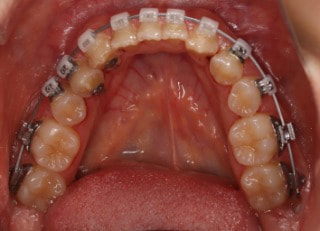

治療前